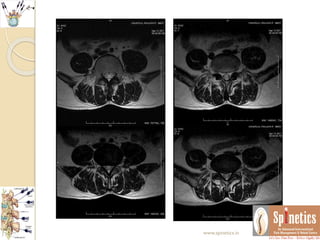

Unusual case

 Neurological behaviour differs in same presenting

spine conditions

 Even though we repeated MRI in one month span as

there is no reccurance what it suggest

 There is resolving annular tear with sequestration

 Many of our patients we routinely found such

herniations which might be too painful to the

patients

 In opposite this patient was not having any

symptoms regarding reccurance of pain

 This the follow-up of more than 2and half years

Unusual case  Neurologicalbehaviour differs in same presenting spine conditions  Even though we repeated MRI in one month span as there is no reccurance what it suggest  There is resolving annular tear with sequestration  Many of our patients we routinely found such herniations which might be too painful to the patients  In opposite this patient was not having any symptoms regarding reccurance of pain  This the follow-up of more than 2and half years www.spinetics.in